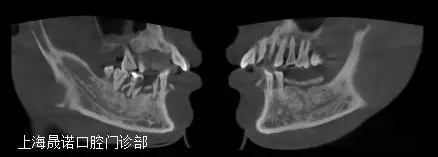

術(shù)前影像檢查分析

640.webp (2).jpg

雙側(cè)后牙區(qū)唇側(cè)不規(guī)則骨缺損,最大骨寬度為7mm,高度尚可。CBCT掃描顯示下頜余留牙牙周支持組織重度喪失和伴根尖周病變、繼發(fā)齲。